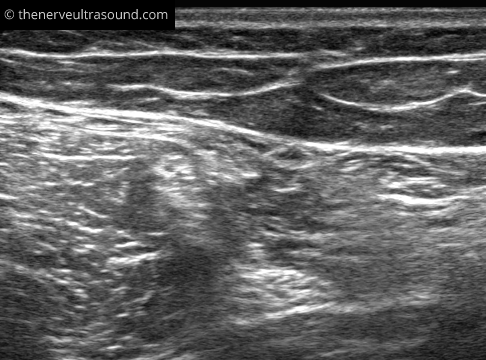

Primary palpation of the groove between the semitendinous and the long head of the biceps femoris muscle makes it easier to find the sciatic nerve in the subgluteal region. Here, the fascia between the two muscles often has an S-shaped aspect pointing to the sciatic nerve deep to the muscles.

The sciatic nerve lies quite superficial at the subgluteal region and the popliteal fossa. In between the nerve runs deeper and might be difficult to identify clearly in obese patients. Starting the scanning more distally at the position E in the knee fold makes it easier to identify the nerve at the positions C and D.

The site of the bifurcation of the sciatic nerve into the tibial and common peroneal nerve is variable. Often the portion of the sciatic nerve forming the tibial or the common peroneal nerve can be already identified much more proximal to the bifurcation.